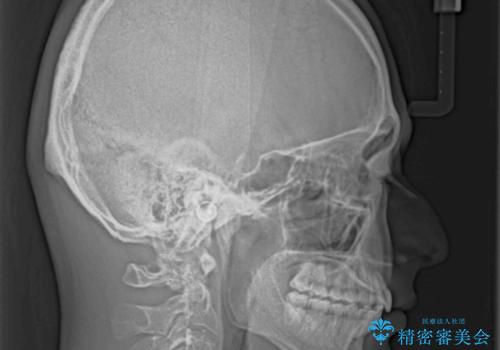

インビザラインで難儀する部分をワイヤー装置にて確実に改善しておくことで、インビザラインのみで行うよりも治療期間を短縮するとともに、より理想的な歯列に近づけて仕上げることができました。